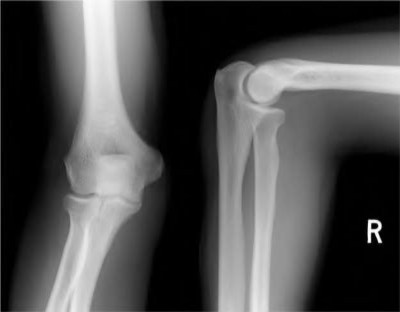

A 35-year-old woman reports wrist pain after a fall onto an outstretched hand. On exam, she has focal tenderness over the wrist snuffbox. A radiograph and CT image are shown in Figures A and B. What is the proper treatment of her injury?